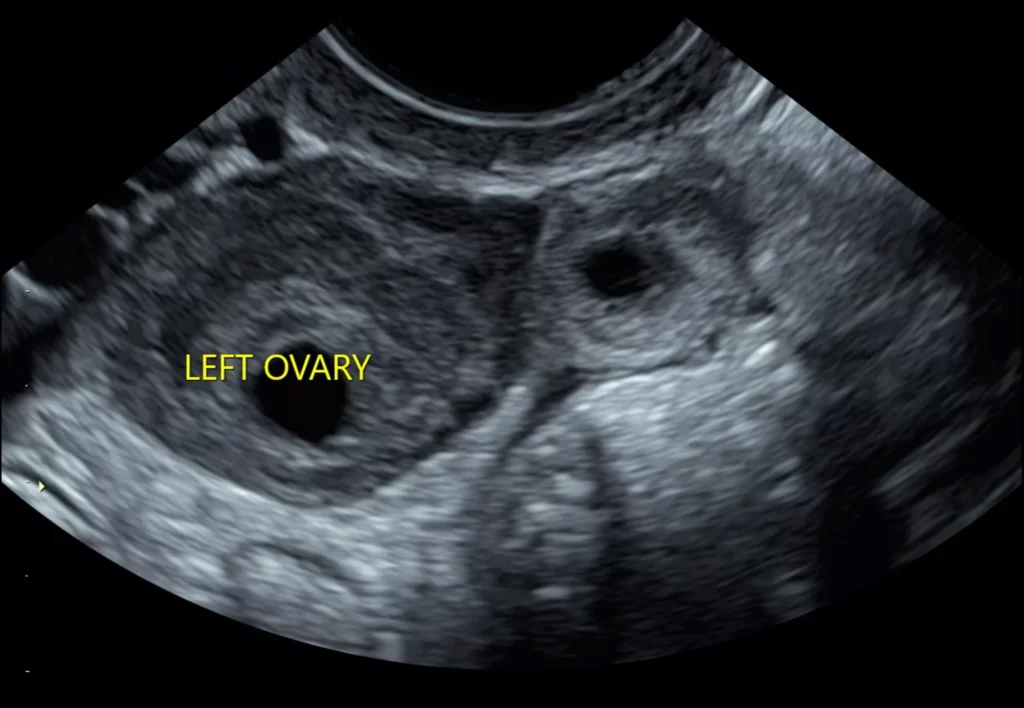

Ovarian Cyst